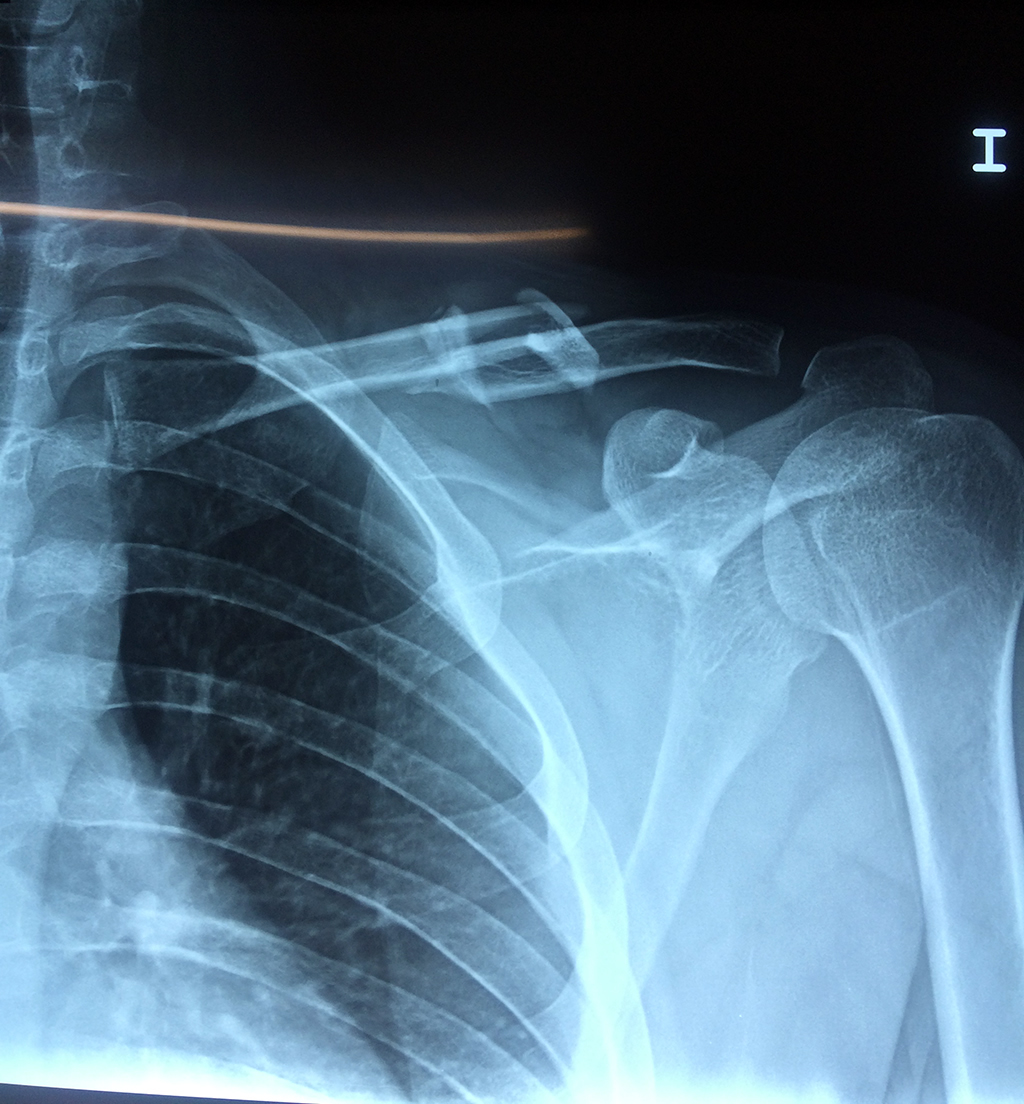

Húmero - Clavícula

La clavícula es un hueso largo, con forma de "S" itálica, situado en la parte anterosuperior del tórax. Junto con la escápula forman la cintura escapular. Se puede palpar por toda su longitud y se extiende del esternón al acromion de la escápula, siguiendo una dirección oblicua lateral y posterior.

Se considera el único medio de unión entre el miembro superior y el tórax. A pesar de su aspecto, similar al de un hueso largo, posee una estructura semejante a la de un hueso plano, ya que carece de epífisis y de diáfisis, lo que la harían entrar dentro de la clasificación de hueso largo. Carece de un canal medular propiamente dicho.